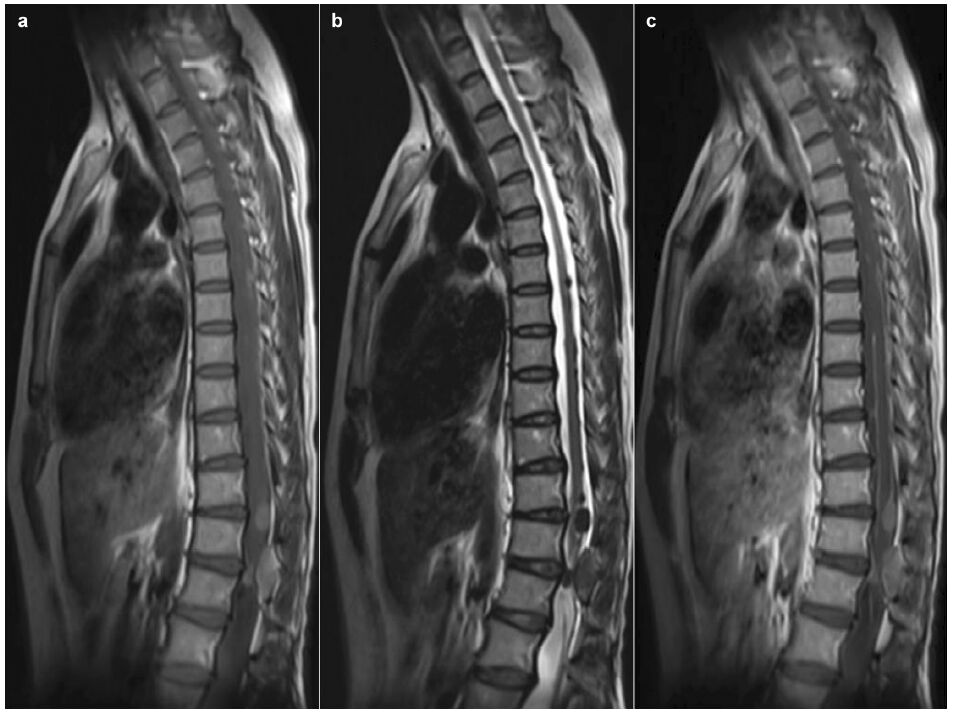

Magnetic resonance imaging (MRI) revealed com-pression and distortion of the spinal cord caused by intraspinal multi-nodules at the level of T6 through L1, which were hyperintense on the T1-weighted MR image (T1WI) and hypointense on the T2-weighted image (T2WI). The MR images obtained after gadolinium-diethylenetriamine pentaacetic acid (Gd- DTPA) injection clearly showed homogenous enhan-cement of the lesions on T1-weighted images (Figure 2). The cervical spine and intracranial lesions were not observed on the series of MR images. Based on the neuroimaging results, intraspinal neurofibroma was suspected. Skin biopsy on the back revealed congenital nevi of the common melanocytic type.

| Figure 2 Sagittal magnetic resonance (MR) images. Multi-nodules of T6 through L1, hyperintense on the T1 weighted image (a), hypointense on the T2 weighted image (b), and homogenous enhancement of the lesions and linear enhancement of the spinal pia materon T1-weighted images (c). |